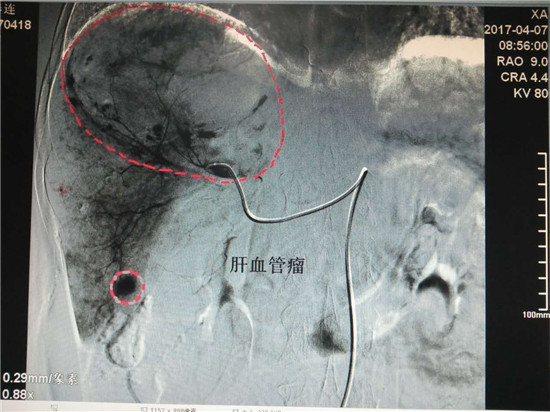

患者孙某,女性,62岁,在我院体检时发现患有巨大肝血管瘤(130mm×88mm),4月7日,在乐鱼在线登录入口介入科行介入微创手术治疗。术前,科主任李建国详细分析评估了病情,组织科室人员制定了严密的手术方案,术中精细操作,在全体医护人员的密切配合下,历时40分钟,成功对患者肝脏巨大血管瘤实施了肝动脉超选择介入栓塞术。治疗过程患者处于清醒状态,无痛苦,术毕生命体征正常,安返病房。

肝血管瘤患者通常是在体检时发现,药物治疗几乎无效,传统的方法是外科手术,但因手术风险大,术后恢复时间长,对身体创伤比较大,成为了患有肝血管瘤患者的最大心病。近年来,肝血管瘤的微创治疗发展非常迅速,具有代表性的肝血管瘤介入治疗逐渐得到推广应用,在我院介入科已经熟练开展,为渭南及周边区域诸多患者带来了福音。